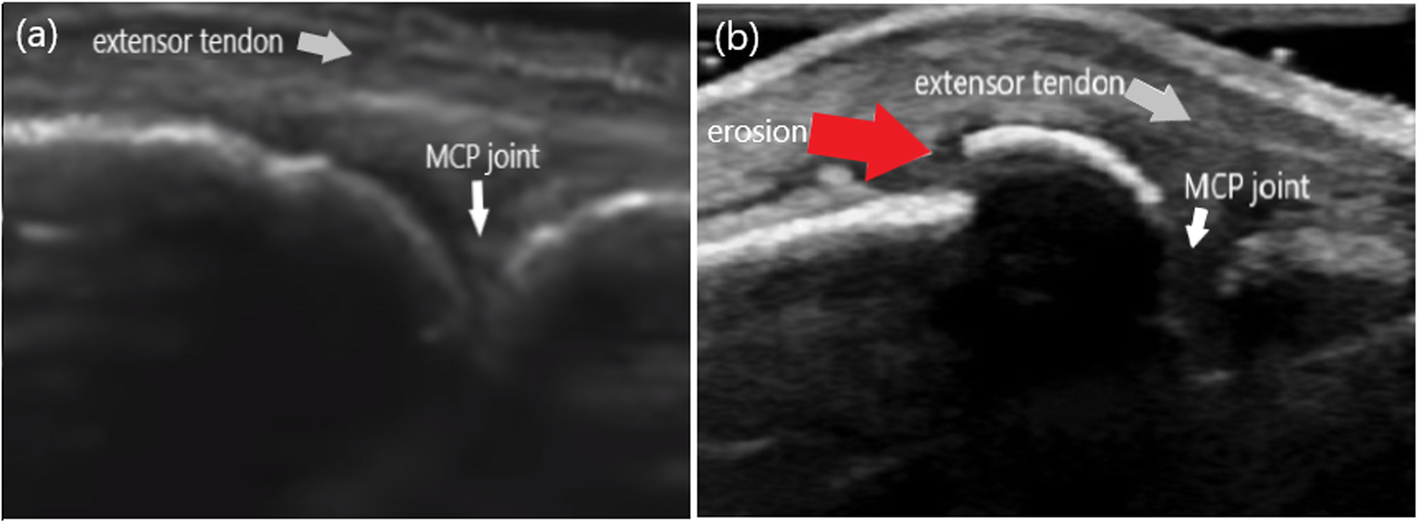

Fig. 2From: A case with Behçet’s disease involving erosive Metacarpophalangeal joint arthritis: the value of ultrasonography in the diagnosis of an ErosionThe longitudinal images of the second MCP joint in dorsal aspect (a): A normal articular surface (white arrow) of the second MCP joint. (b): The appearance of the erosion (red arrow) as the step-down contour defectBack to article page